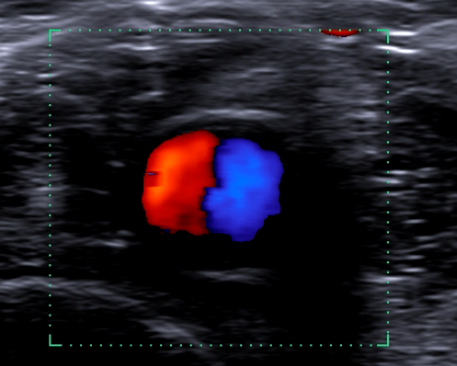

Ecografía de rodilla: imagen anecogénica presanserina sin captación. A nivel de arteria poplítea izquierda se detecta el signo del Yin y Yang.

El signo ecográfico del Yin y Yang nos plantea la existencia de un aneurisma arterial o pseudoaneurisma. La presencia de un diámetro arterial mas de 1,5 el valor de la normalidad nos inclinarían en favor de aneurisma. La afectación de solo 1 capa y la presencia del cuello nos inclinaría por pseudoaneurisma. El flujo turbulento por una dilatación anatómica (bulto carotídeo) o patológica como el caso que nos ocupa nos orienta a placa de ateromatosis. Deben describirse las características de dicha placa (tamaño, posición, ecolucencia) y completar el estudio de las VPS y la morfología de las curvas arteriales. La realización del ITB nos permite descartar la presencia de Enfermedad Arterial Periférica.